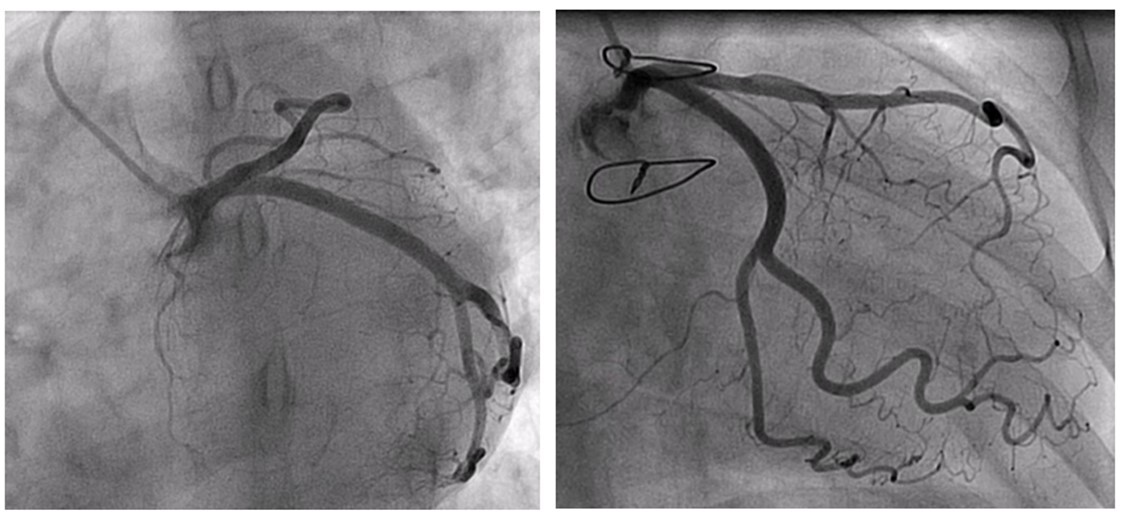

Aortography showed no dilatation of the aortic root or ascending aorta. Intravascular ultrasound (IVUS) at maximum depth showed normal wall coronary structure, no atheromatous stenosis, and no dissection. However, vessel compression was observed in the proximal areas of the LAD and Cx (Figure 3), suggesting an extracoronary structure not identified by this technique (Videos 1-5).